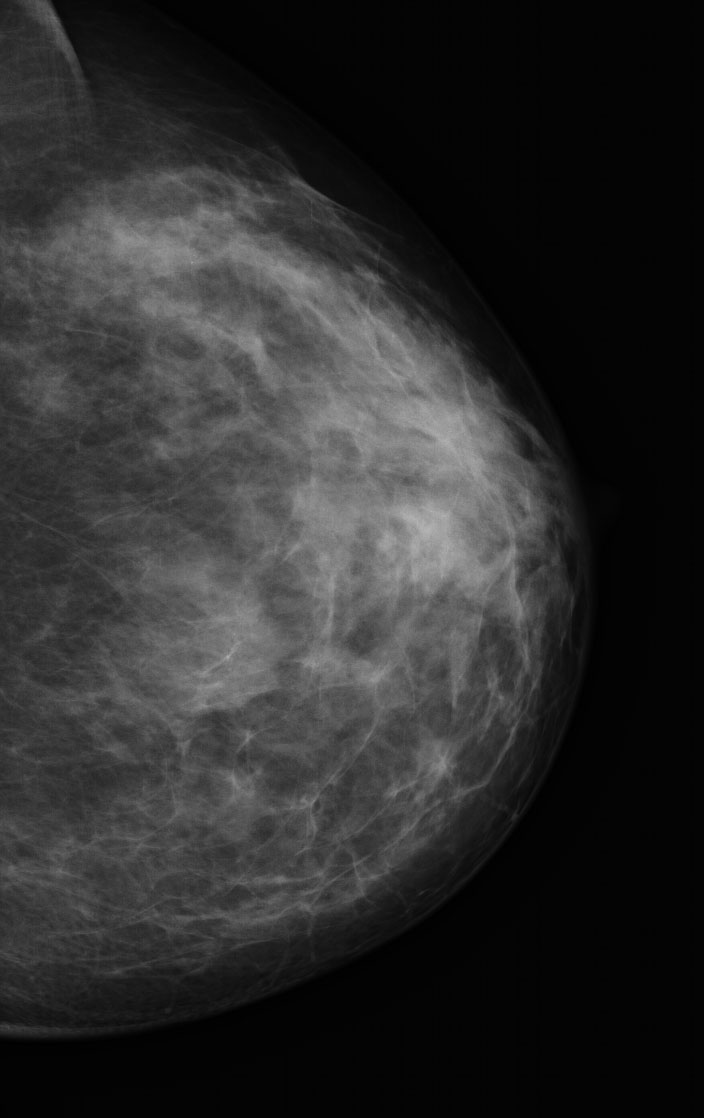

Dr. Alberto Gallardo (patòleg) i Dra. Ferrer (radiòleg).

Clínica Girona

Paciente varón de 54 años con tumoración en unión de cuadrantes superiores de mama izquierda que parece depender del músculo. Se realiza punción con aguja fina.

Se adjunta fotografías de las extensiones, bloque celular y mamografía y ecografía.

Dra. Mª Jesus Diaz Ruiz (radiòloga) i Dra. Carme Vergara Larrosa (Patòloga).

Althaia, xarxa assistencial universitària de Manresa

Dona de 50 anys, en cribatje de mama des dels 40; assimtomàtica. En una de les mamografies es troben calcificacions en QIE de mama esquerra de nova aparció.

En els controls succesius aparició de tumoració en QIE mama esquerra amb traducció radiològica de quist complicat de 13mm.

Es realitza PAAF: el diagnòstic es de abundant cel·lularitat inflamatoria, negatiu per cèl·lules malignes. Material citològic compatible amb quist.